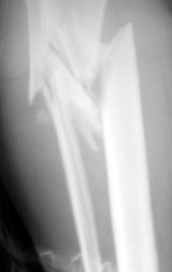

Re: открытый оскольчатый в/3 голени

Рентгенограмма при поступлении. Думаю на ней видно распространение линии перелома вниз

На снимке не видно, как далеко по диафизу идет линия перелома. На мой взгляд, лучше сделать еще один снимок, как бы не пришлось делать АВФ из 4

опор.